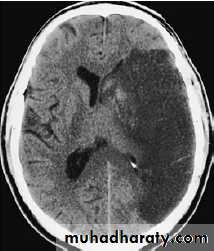

NEUROIMAGINGX-rays (plain X-rays, computed tomography (CT), myelography and angiography), magnetic resonance (MR imaging-MRI, or MR angiography-MRA), ultrasound (Doppler imaging of blood vessels), and radioisotopes (single photon emission computed tomography-SPECT, and positron emission tomography-PET).

A- CT scan